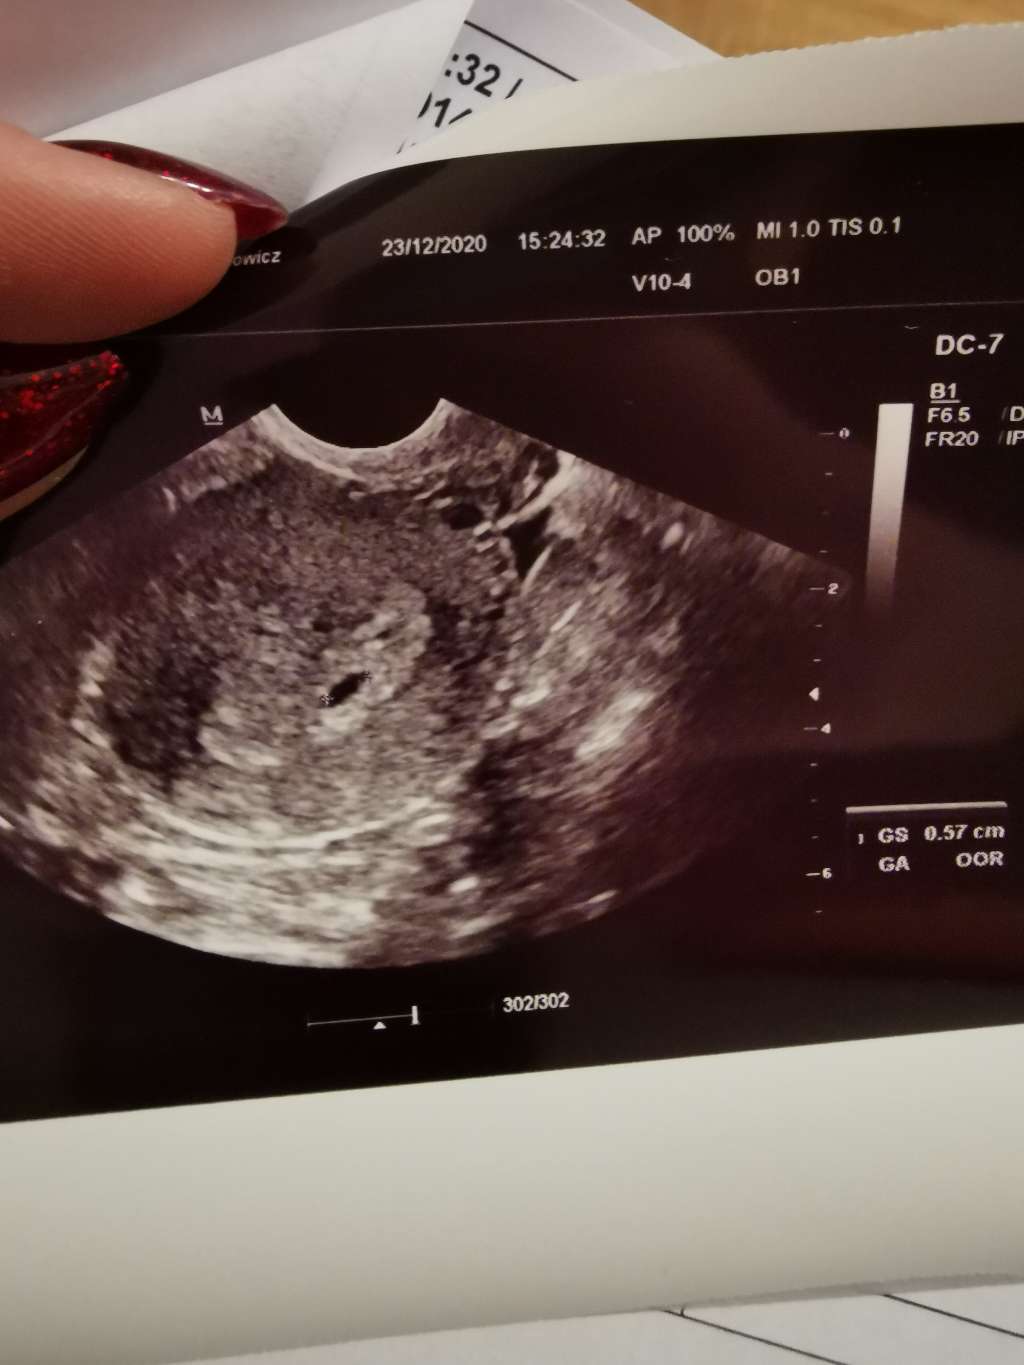

Lekarz mi tłumaczył że może być to spowodowane dwoma pęcherzykamiZrobilam bete i przyrost 48% w ciagu po ad 48h kurcze malo. Ale tez niewiem czy juz nie za daleki etap ciazy na te przyrosty. Kurcze no teraz do wtorku oszaleje chyba. [emoji31]

Nie wiem czemu ale ja tu widzę chyba podwójnie pęcherzykJa Po badaniu. Pęcherzyk rośnie, jeszcze zarodka nie było widać ale jest jak na razie wszystko dobrze7 stycznia kolejna wizyta

Lekarz mi tłumaczył że może być to spowodowane dwoma pęcherzykami

Oprocz tego że masz ładne zdjęcia, to masz odjazdowe paznokcieJa Po badaniu. Pęcherzyk rośnie, jeszcze zarodka nie było widać ale jest jak na razie wszystko dobrze[emoji16] 7 stycznia kolejna wizyta[emoji846]